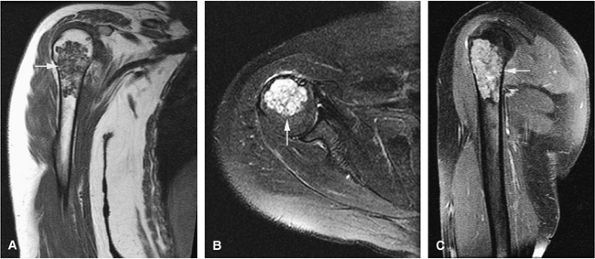

FIGURE 14-21 ● (A) Coronal T1-weighted image shows a low-signal-intensity proximal humeral enchondroma (arrow). (B) On an axial fat-suppressed T2-weighted fast spin-echo image, the chondroid matrix is hyperintense (arrow). (C) Sagittal fat-suppressed T1-weighted image after administration of intravenous gadolinium demonstrates enhancement of the lesion (arrow).